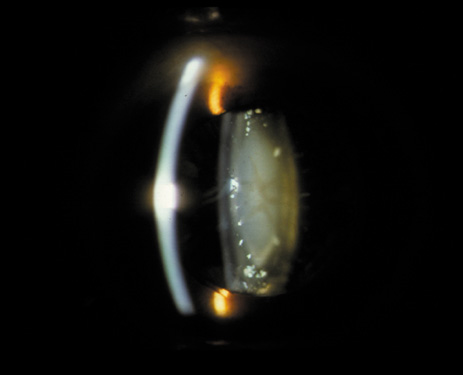

Nuclear cataracts tend to progress slowly. The refractive index of the lens changes as the nucleus progressively hardens, which usually results in increasing myopia.20,21 In some patients this is accompanied by optical distortion, especially of distant images, while near vision remains unaffected. A nuclear cataract is best seen with the narrow-beam direct illumination employed by the slit-lamp, which reveals the color and generalized haze or opalescence of the nucleus. In the early stages, the two halves (cotyledons) of the embryonic nucleus remain visible (Fig. 3). Later the entire nucleus appears as a homogeneous mass in contrast to the cortex (Fig. 4). Retroillumination may show the “oil droplet” effect (Fig. 5). Sometimes one may notice crystals in the lens nucleus (known as a Christmas tree cataract; Fig. 6A and B).

Fig. 3. Early nuclear cataract. Note the “cotyledons” in the nucleus.

Fig. 4. Advanced nuclear cataract. Note the homogeneous nuclear opacity.

Fig. 5. “Oil droplet” appearance of a pure nuclear cataract seen on retroillumination examination.